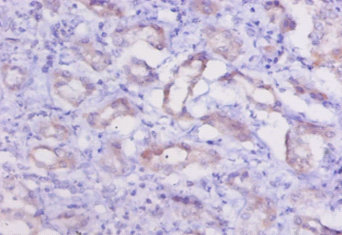

ApplicationELISA, IHC; Recommended dilution: IHC:1:10-1:100